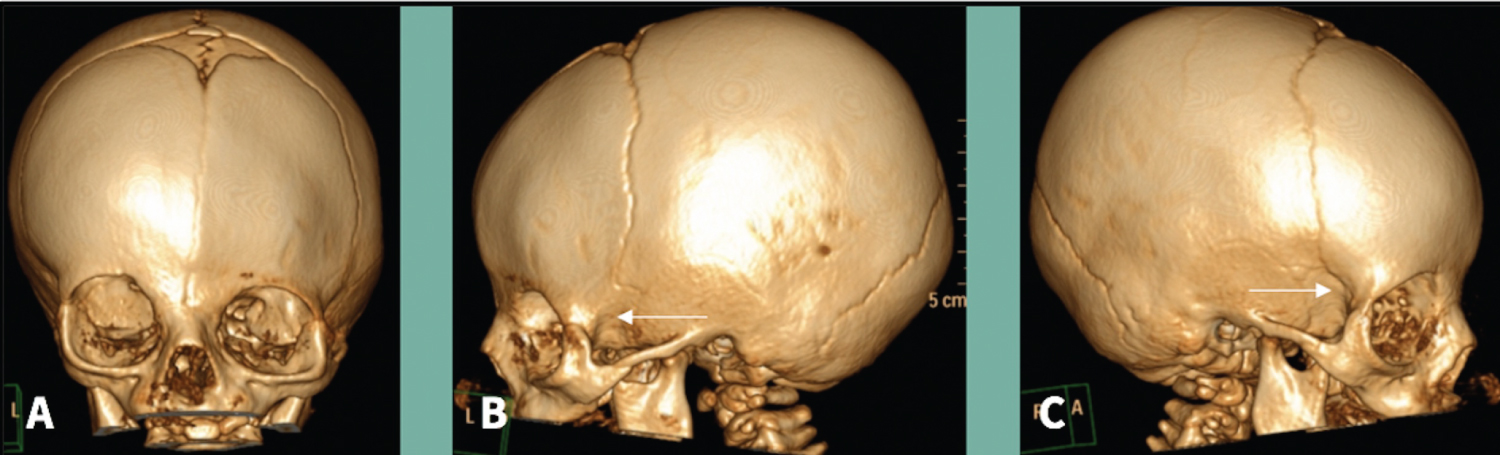

A 7-5 months-old male patient came to our consultation referred for anterior plagiocephaly with a suspected diagnosis of coronal synostosis. The patient was the first-born from a non- consanguineuos young couple. Antenatal and obstetrical history was otherwise irrelevant. He presented to our examination with a left frontal flattening with a ipsilateral downward eyebrow and supraorbital rim. Nasal tip was desviated to the left side and the chin centered on the midline. Ophtalmological examination excluded strabismus or amblyopia. CT scan revealed a left frontosphenoidal suture fusion and a patency of the right frontosphenoidal suture as shown in the Figure 3.

Figure 3: A) Three-dimensional CT reconstruction shows frontal; B,C) Lateral views. The arrow in image B represents left frontosphenoidal fusion and in C a right frontosphenoidal suture patency. View Figure 3